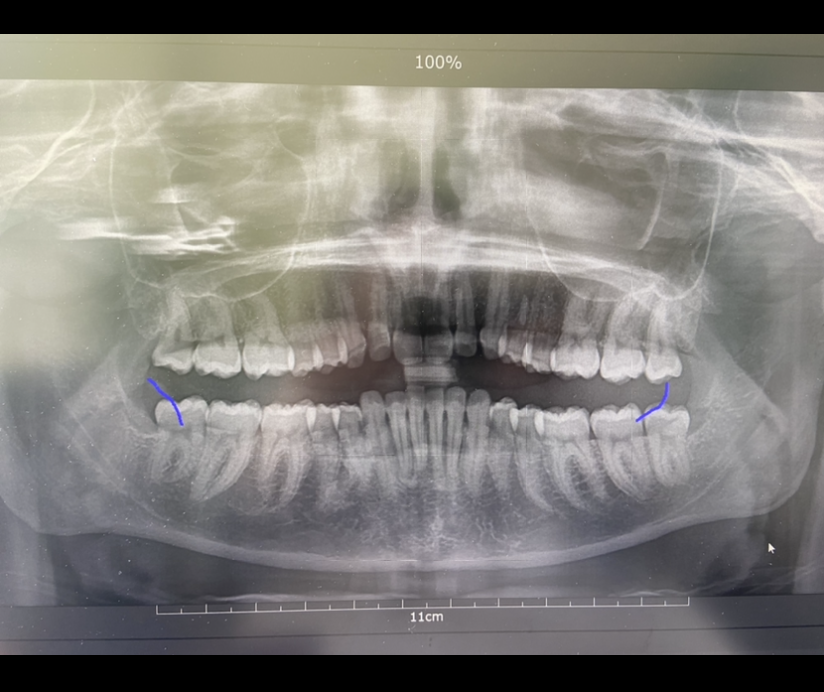

Какво може да причини постоянна болка след екстракция на нерв на зъб?

Постоянната болка след екстракция на нерв на зъб може да бъде причинена от неправилно лечение, неправилно кореново запълване или възпаление на кореновите канали. Обикновено болката трябва да намалее в рамките на 2-3 дни след процедурата. Ако болката продължава, препоръчително е да се консултирате със зъболекар.